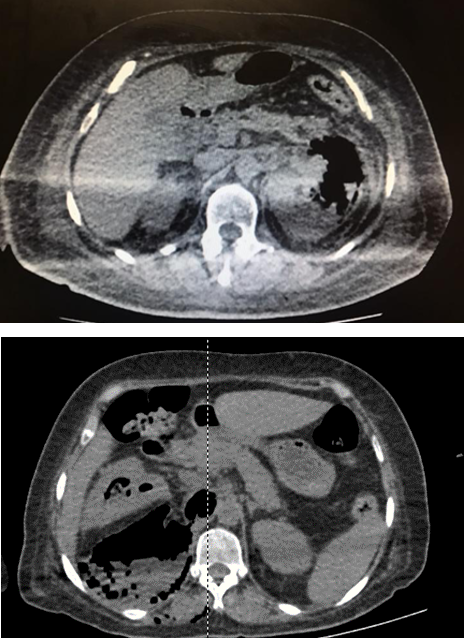

| 3A. Extensión del gas al espacio perinéfrico. (Imagen 3) | ||

| 3B. Extensión del gas al espacio paranéfrico. (Imagen 3) | ||

Imagen 3 a) Huang 3a.- Presencia de gas en espacio perirrenal. b) Huang 3b.- Presencia de gas en espacio pararrenal.